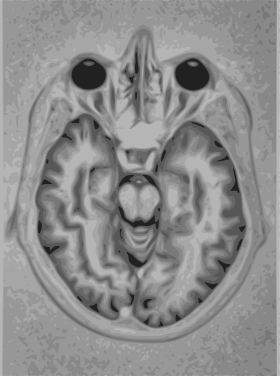

A brain MRI representation

A magnetic resonance imaging instrument (MRI scanner), or "nuclear magnetic resonance (NMR) imaging" scanner as it was originally known, uses powerful magnets to polarize and excite hydrogen nuclei (i.e., single protons) of water molecules in human tissue, producing a detectable signal which is spatially encoded, resulting in images of the body.[4] The MRI machine emits a radio frequency (RF) pulse at the resonant frequency of the hydrogen atoms on water molecules. Radio frequency antennas ("RF coils") send the pulse to the area of the body to be examined. The RF pulse is absorbed by protons, causing their direction with respect to the primary magnetic field to change. When the RF pulse is turned off, the protons "relax" back to alignment with the primary magnet and emit radio-waves in the process. This radio-frequency emission from the hydrogen-atoms on water is what is detected and reconstructed into an image. The resonant frequency of a spinning magnetic dipole (of which protons are one example) is called the Larmor frequency and is determined by the strength of the main magnetic field and the chemical environment of the nuclei of interest. MRI uses three electromagnetic fields: a very strong (typically 1.5 to 3 teslas) static magnetic field to polarize the hydrogen nuclei, called the primary field; gradient fields that can be modified to vary in space and time (on the order of 1 kHz) for spatial encoding, often simply called gradients; and a spatially homogeneous radio-frequency (RF) field for manipulation of the hydrogen nuclei to produce measurable signals, collected through an RF antenna.

Like CT, MRI traditionally creates a two dimensional image of a thin "slice" of the body and is therefore considered a tomographic imaging technique. Modern MRI instruments are capable of producing images in the form of 3D blocks, which may be considered a generalization of the single-slice, tomographic, concept. Unlike CT, MRI does not involve the use of ionizing radiation and is therefore not associated with the same health hazards. For example, because MRI has only been in use since the early 1980s, there are no known long-term effects of exposure to strong static fields (this is the subject of some debate; see 'Safety' in MRI) and therefore there is no limit to the number of scans to which an individual can be subjected, in contrast with X-ray and CT. However, there are well-identified health risks associated with tissue heating from exposure to the RF field and the presence of implanted devices in the body, such as pace makers. These risks are strictly controlled as part of the design of the instrument and the scanning protocols used.

Because CT and MRI are sensitive to different tissue properties, the appearance of the images obtained with the two techniques differ markedly. In CT, X-rays must be blocked by some form of dense tissue to create an image, so the image quality when looking at soft tissues will be poor. In MRI, while any nucleus with a net nuclear spin can be used, the proton of the hydrogen atom remains the most widely used, especially in the clinical setting, because it is so ubiquitous and returns a large signal. This nucleus, present in water molecules, allows the excellent soft-tissue contrast achievable with MRI.